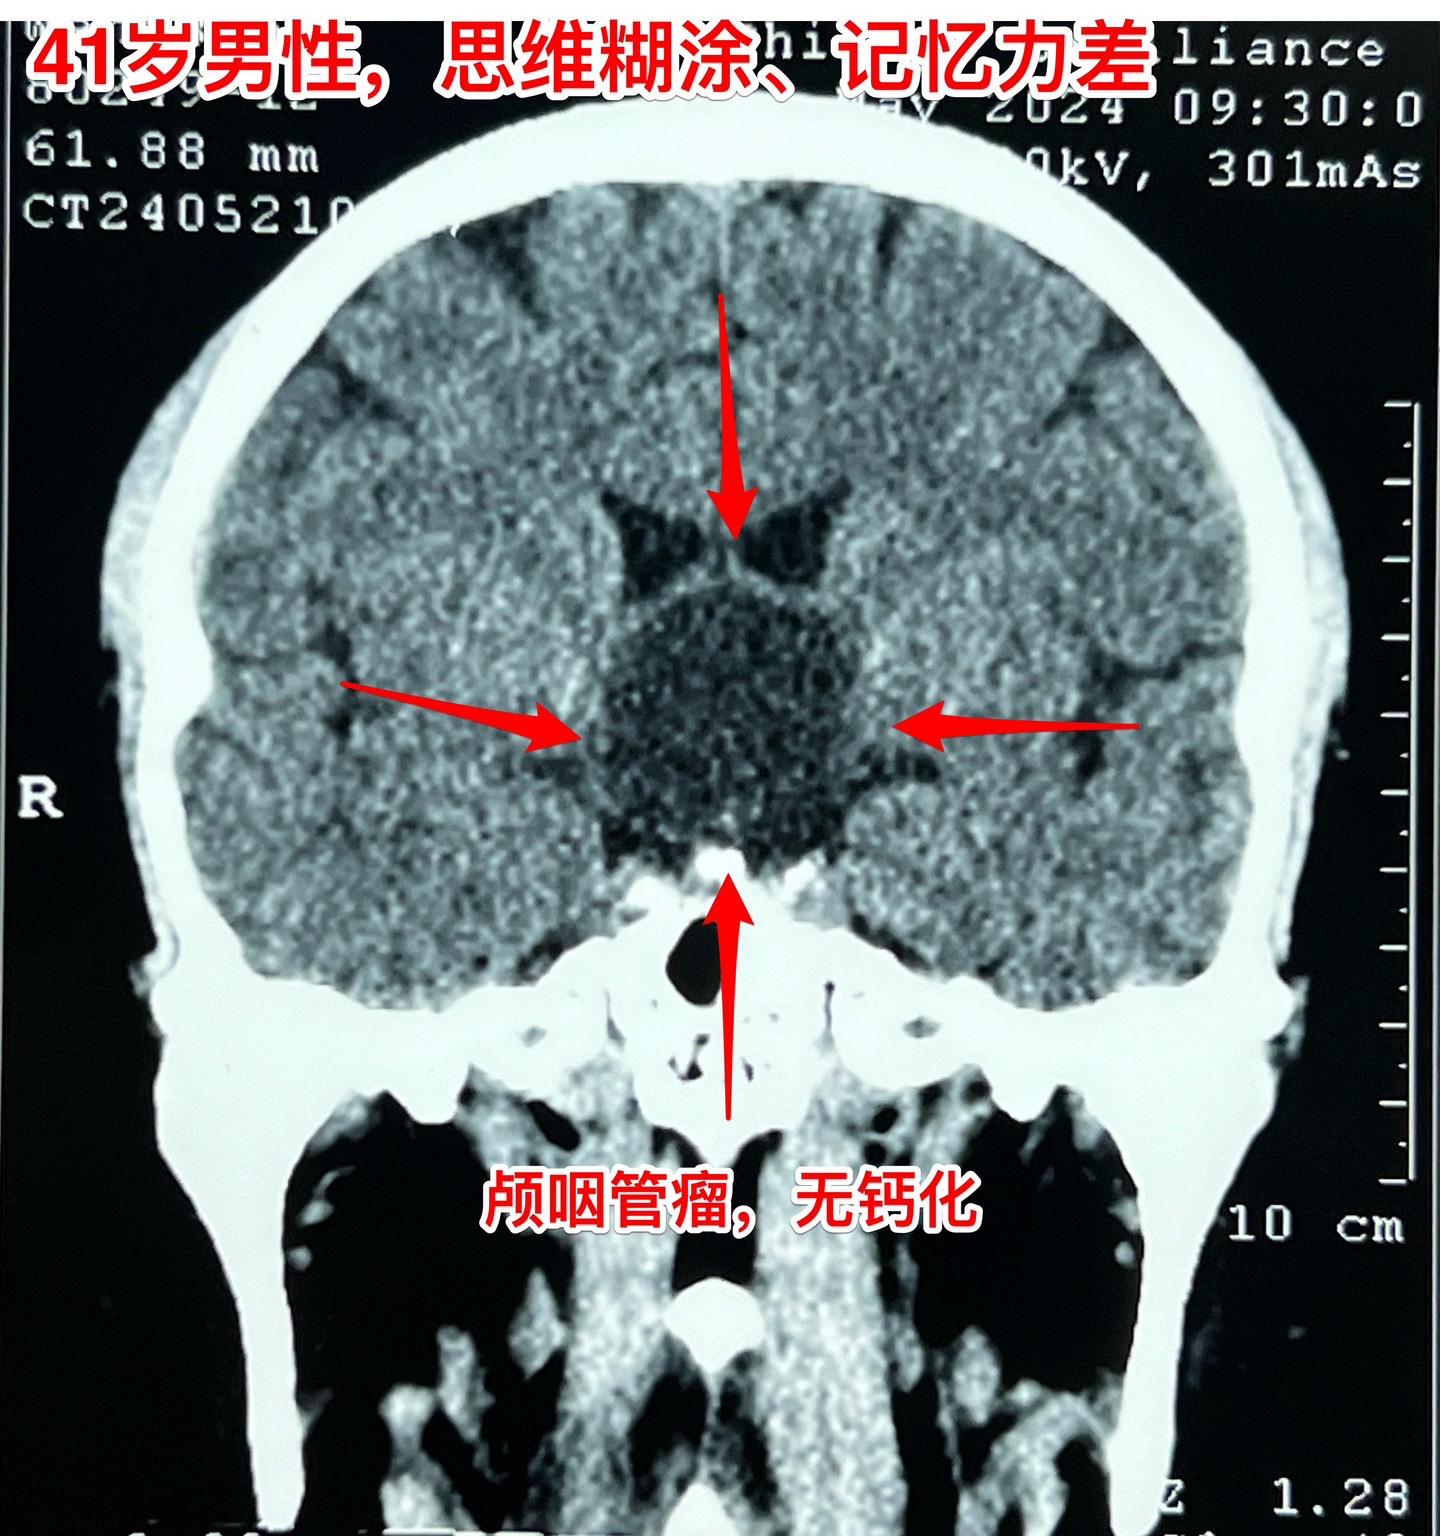

5月31日的颅咽管瘤手术。41岁山西男性,因思维糊涂、记忆力差发现鞍区肿瘤,为乳头型颅咽管瘤。 常规的经额底纵裂入路,将肿瘤完全切除。手术后病人的精神状态很好。 五月份的一共完成21台手术,其中20台为颅咽管瘤(今年一共80个颅咽管瘤手术),另一台为鞍区皮样囊肿! 在神经外科界,鞍区肿瘤的治疗是很有挑战性的![呲牙